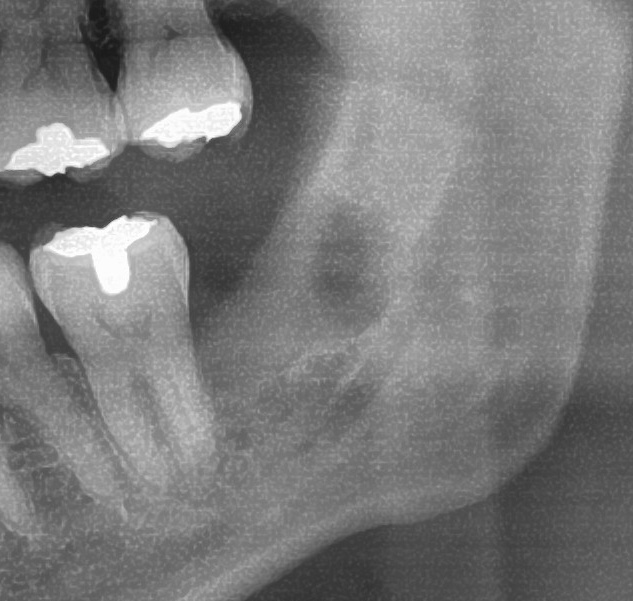

次にパノラマ写真を撮影してみると、左下の親知らずは手前の歯を押すように斜めに生えているのが確認できました。

さらに、下顎の親知らずは下歯槽神経に非常に近いところに生えている場合もあるため、CTも撮影し詳しい解析を行います。

親知らずが生えている位置が、神経に近い、あるいは神経に当たっている場合は、大きな病院に紹介する場合もあります。

親知らずの根っこは下歯槽神経から近い距離にありますが、抜歯は可能との診断でした。